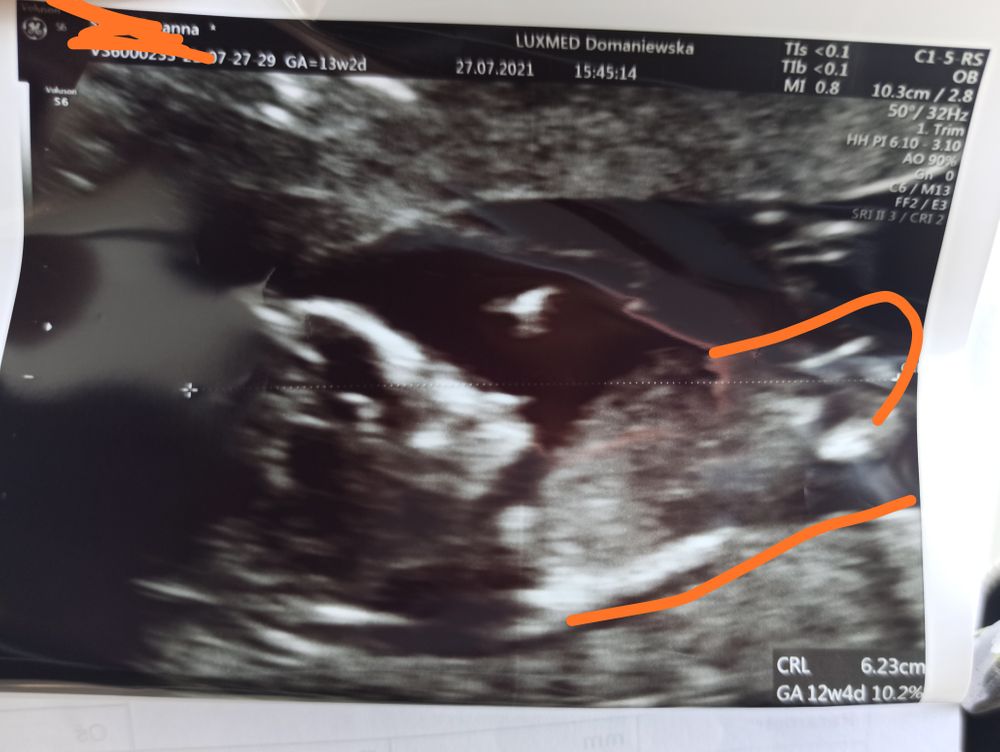

Вот только то, о чем так волновалась - пол - так сегодня и не узнала, но пока смотрела, теперь уверенна, что девочка (насмотрелась видео о том, как выглядит половой бугорок на этом сроке). Паралельно позвоночнику - значит девочка. А у вас как было? 🥰

На вашем фото не определить кто. Если вы бугорок хорошо во время узи сами видели в более удачно ракурсе, то еще может быть.

Ani S, Ну если это точно половой бугорок на фото, то похоже) Просто фото немного неудачное, он как-будто не совсем в кадре и детализация не такая как хотелось бы. У меня на скрининге прям все четко видно было, если бы было по качеству как у вас, то даже не предполагала бы кто))